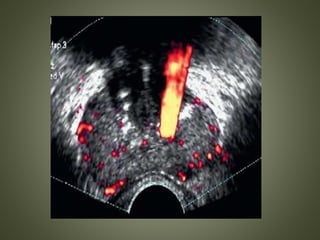

COLOR AND POWER DOPPLER IMAGING

• Detection of neovascularity associated with

cancer

• Especially attractive to find isoechoic cancer

Pitfalls

• Not all cancers are vascular.

• Capsule of the prostate is very vascular,

especially at the base and apex, and can mimic

neovascularity.

• Prostate calcifications and corpora amylacea

cause considerable Doppler artifact and may

prevent diagnostic studies

Axial view shows extensive echogenic material, both calcifications and corpora amylacea

(arrows), along the surgical capsule and peripheral zone. This has no clinical significance and

usually is not palpable. It hinders ultrasonic visibility. Doppler examination of same patient

shows the extensive Doppler noise artifact caused by the calcifications. Virtually all the visible

color is artifactual.